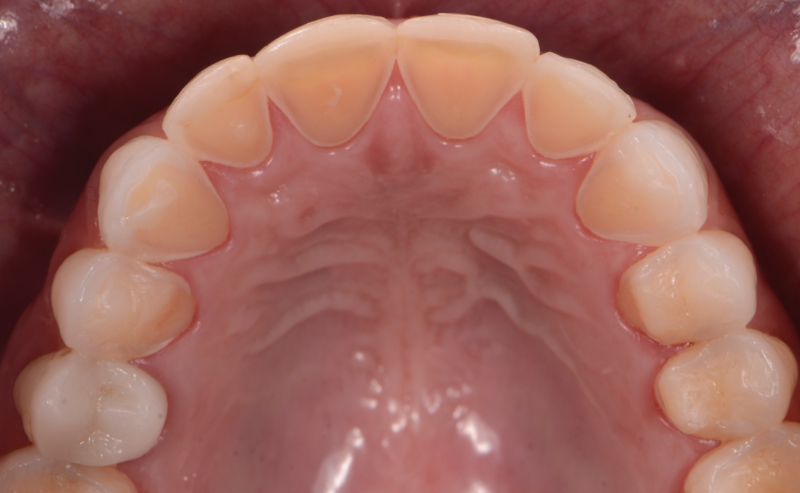

Self-induced vomiting increases the risk of dental erosion by a factor of 5.5 compared to healthy controls. These intrinsic erosion lesions are most commonly found on the palatal surfaces of the maxillary teeth, followed by the occlusal and then the buccal surfaces (Figs. 1–5).